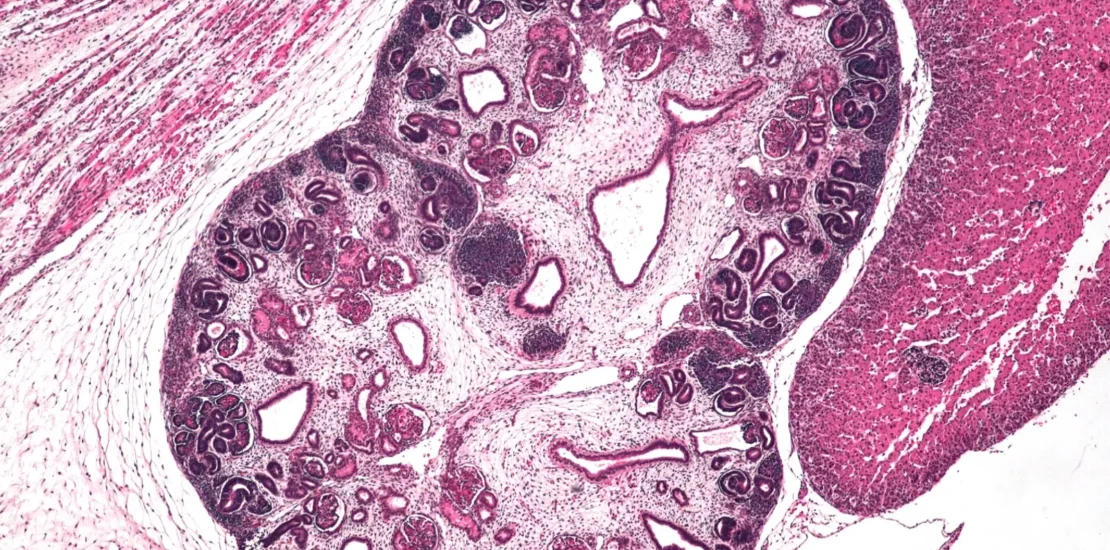

En un avance científico de gran relevancia, un equipo de investigadores del Centro Médico Sheba y la Universidad de Tel Aviv ha logrado cultivar con éxito organoides de riñón humano, es decir, cultivos 3D sintéticos de órganos, a partir de células madre de tejido renal.